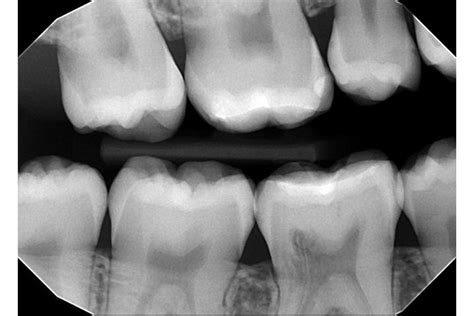

Zlom Zoba in Druge Poškodbe

Poleg resnejših zlomov, ki vplivajo na skelet, se lahko med nosečnostjo ali med aktivnimi otroškimi igrami pojavijo tudi manjše poškodbe, kot je zlom zoba. To se lahko zgodi "pri padcu s kolesa, skiroja, rolke, pri igranju nogometa, borilnih veščinah ali v prometni nesreči." V takih primerih je pomembno, da starši vedo, kako reagirati, saj lahko panika ovira pravilno oskrbo.

V primeru poškodbe zoba, dlesni ali ust, je ključnega pomena hitra in pravilna reakcija. Mag. Marko Miljavec, dr. dent., svetuje, kako ravnati, da bi se zmanjšale posledice in pospešilo okrevanje.